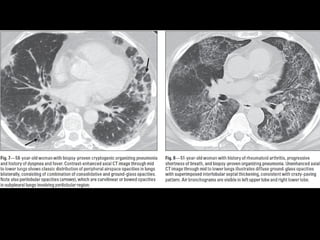

COP CT

• Consolidaciones parcheadas

• Broncograma aéreo Signo halo inverso

• Vidrio esmerilado periférico o peribroncovascular

• Crazy paving

• LI

• Nódulos, cavitarse

• Puede simular neumonía

• Reticulación subpleural

• Derrame pleural

Bilateral or unilateral patchy alveolar airspace consolidation is revealed,

often subpleural and peribronchial in location and mainly in the lower

zones.

Generally, the infiltrates gradually enlarge from their original size or

new infiltrates appear.

Consolidation is often nonsegmental and varies from 2 to 6 cm in

diameter.

Cavitary BOOP that mimics tuberculosis and cavitating opacity after

lung transplantation has been reported.

An air bronchogram may be present.

Nodules 3-5 mm in diameter are seen in approximately one half of

patients; nodules may be migratory.

Basal linear opacities are linked to a poorer prognosis.

Unilateral focal or lobar consolidation occurs in 5-31% of patients.

Miliary pattern is rare.

Pleural thickening occurs but pleural effusions are rare.